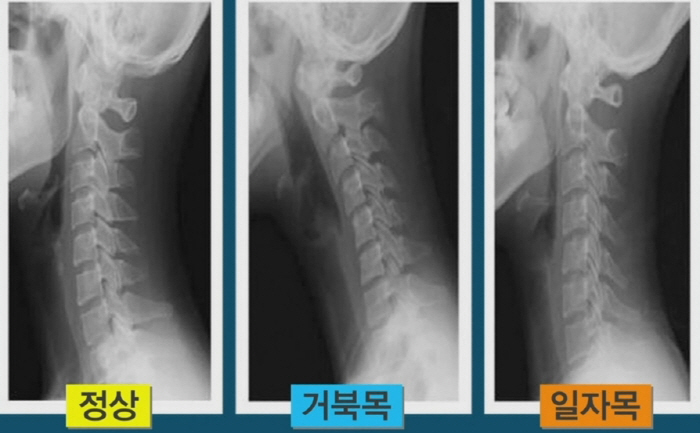

목디스크 증상 2. 목 자세

목디스크 증상 목 자세이고요. 현대인들은 스마트폰이나 모니터를 많이 사용하다보니 목이 앞쪽으로 당겨져있는 것처럼 자세를 많이 취하게 된다 하였습니다. 이런 자세는 정상적인 목뼈를 전환 시켜 여러분이 아시는 거묵목 증상이 나타나게 되는 이유가 되는 것입니다.